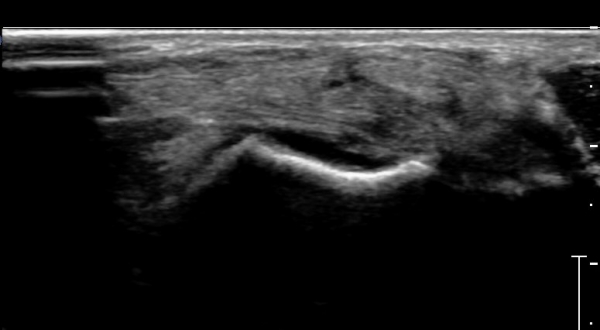

ÇϺΠ½ÅÀü ¶ì(inferior extensor retinaculum) ÀÇ frondiform Àδë Á¾´Ü¸é°Ë»ç¿¡¼­

frondiformÀÎ´ë ½ÉºÎ°¡Áö ÁÖº¯ ¼ö¾×Àú·ù°¡ °üÂûµÇ°í Á·±Ùµ¿ °æºÎÀδ밡 ³Ê¹« ¶Ñ·ÇÈ÷

°üÂûµÈ´Ù(»çÁø 5, 6, 7).